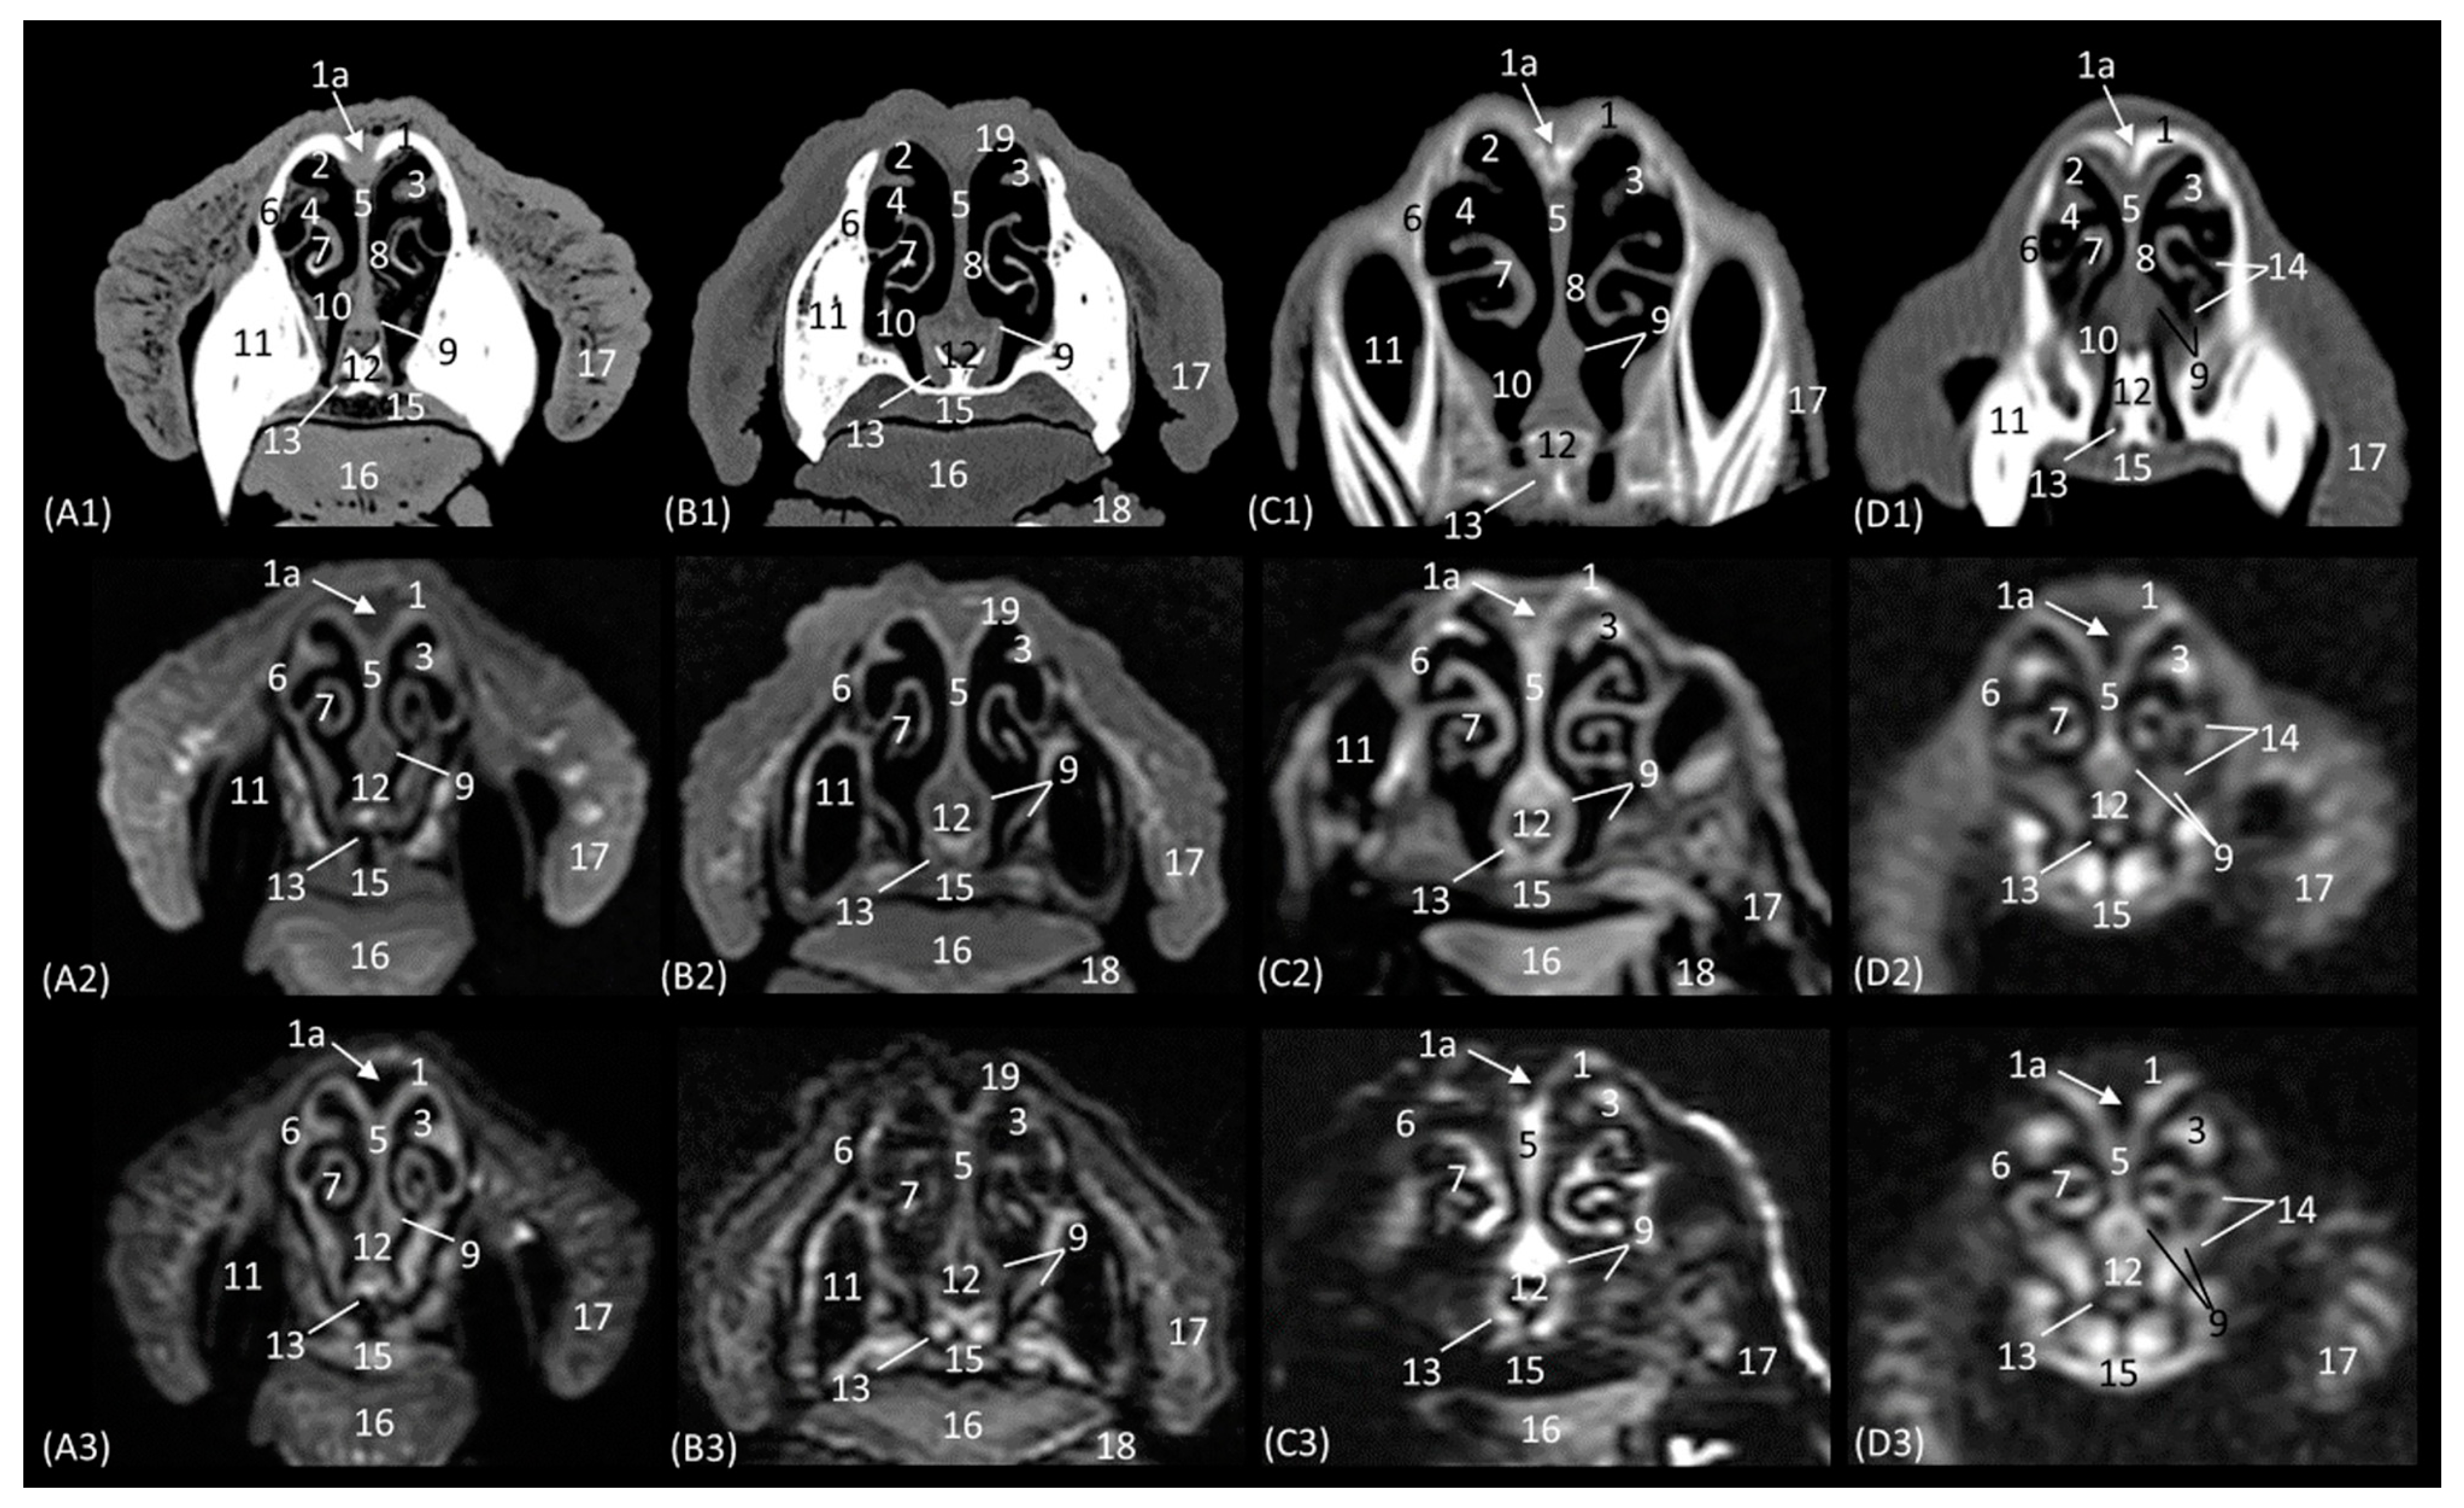

The next level is represented in Figure 6(A1–D3). Figure 6(C1) shows the section where the external plate of the frontal bone ventrally relates to the ethmoid bone and frontal sinus in the cheetah, since at this level in this species, the nasal bone is no longer sectioned. In the nasal cavity, it is worth highlighting the presence of the infraorbital canal. It can be identified both on CT and MRI in a rounded area that is hypoattenuated and hypointense, respectively, with respect to the maxillary bone. In this section, the third endorturbinate is observed, entering and intertwining between the dorsal and ventral nasal concha. It is evident again in these images that the nasal conchae and endoturbinates in the lion are much thinner than in the other three species, resulting in much wider meatuses. In this section, we can, again, see how the ventral nasal concha in the domestic cat has two bony starts from the maxilla, unlike the big cat species, which only have one.

A more caudal section of the nasal cavity is depicted in Figure 7(A1–D3). The bony framework that supports the nasal cavity at this level is composed dorsally of the nasal bone (only in the lion, as it extends more caudally), the external lamina of the frontal bone (squama), the maxillary bone (palatine process), and the vomer. In addition, the zygomatic bone is observed in the lion and in the domestic cat. At this level, the tectorial plate of the ethmoid bone can already be seen in the leopard and cheetah, although it is not yet visible in the lion, delimiting the frontal sinus ventrally, which also occurs in the domestic cat in a more rostral view (Figure 6(D2,D3)). In the lion, the frontal sinus develops much further caudally than in the other species. In addition, only in felids does the frontal sinus present a lateroventral opening towards the nasal cavity. Moreover, the bones of the roof (nasal and frontal bones) have a much greater thickness in lions than in the other species. The vomer bone in this plane already appears in its full extension: in large cats, it is composed of two long vertical arms and a short trunk, while in the domestic cat, it develops with a much longer trunk and shorter arms. In the nasal cavity, we observed the dorsal, middle, and ventral nasal conchae; the third endoturbinate; the vomeronasal organ; the cavernous plexuses; and the infraorbital canal. The vomeronasal organ was observed with a wide duct in the cheetah and a small duct in the leopard, and a duct was not observed in the lion or the cat. In this cross-section, the middle nasal concha is identified for the first time but is camouflaged by the extensive development of the third endoturbinate at this level. The ventral nasal concha shows ventral coiling and is dorsally flattened in the leopard. In the lion, the dorsal and ventral conchae are large but narrow, and in cheetahs and cats, they are smaller.

The next section level is shown in Figure 8(A1–D3), which allow the zygomatic bone to be identified in all species. The bony structures that make up the nasal cavity at this level is established dorsolaterally by the external and orbital surface of the frontal bone, the lacrimal bone, and the zygomatic bone; ventrally by the vomer bone, as well as the palatine bone; ventrally to the frontal sinus by the tectorial plate of the ethmoid bone; and medially by the cartilage of the nasal septum. This section also highlights the significant thickness of the frontal bone in lions, which is unlike the other feline species. It is observed to be hyperattenuated on CT, while on MRI, it is observed with a hypointense cortical with a hyperintense medullary cavity. Furthermore, at this level, the frontal sinus does not yet appear in the lion, while in the rest of the species, the bony septum of the frontal sinus can already be seen, and inside the nasal cavity, the first, second, and third ectoturbinates are already identifiable. The nasal septum is already ossified at this level, since it appears to be hyperattenuated on CT and hyperintense on MRI, although only very slightly in the lion. The bony component of the hard palate at this section is provided by the palatine bone. Within the nasal cavity at this level, we highlight the three ectoturbinates, the dorsal, middle, and ventral nasal conchae, the third endoturbinate, the vomeronasal organ, the nasal cavernous plexuses, and the lateral nasal gland. The ventral nasal concha is already identified as very small at this level. However, the third endoturbinate reaches its greatest development in this view. The tectorial plate, which occurred in a more rostral view in the cat, also joins more ventrally in the leopard and cheetah to leave the necessary space for the development of the ectoturbinates. From the dorsal to the ventral, the first ectoturbinate develops more laterally, the second more medially, and the third again more laterally. Also notable at this section is the identification of the lateral nasal gland in the four species in the maxillary recess, with an intermediate attenuation in CT and an intermediate signal intensity in MRI.

The last transverse plane of the nasal cavity from this CT and MRI study is presented in Figure 9(A1–D3). The bony part of the nasal cavity at this level is represented dorsally by the external plate of the frontal bone; laterally by the orbital surface of the ethmoid bone and the wing of the presphenoid bone; and ventrally by the basal plate of the ethmoid bone, the vomer, and the palatine bone. In addition, ventral to the frontal sinus, the tectorial plate of the ethmoid bone was observed, as was, medially, the bony nasal septum. Ventrally to the nasal cavity, the choanae were observed. The vomer bone ends at this level, and it differs among the species. In the leopard and the lion, the vomer has an oval morphology, while in the cheetah, it is arrow-shaped, and in the domestic cat, it is smaller and rounded. The nasal septum, at this section level, can already be observed as ossified in the four species, hyperattenuated in CT, and in MRI, it has a higher signal intensity than in the more rostral sections. The nasal cavity of this section is made up of three ectoturbinates, the dorsal and middle nasal concha, and the third and fourth endoturbinates. The choanae were observed in all four felids and were delimited dorsally by the basal plate of the ethmoid bone and ventrally by the perpendicular and horizontal plate of the palatine bone. In this last plane, the frontal sinus was seen in the lion, along with the development of the three ectoturbinates, which at this level appeared to be larger in all four species. Furthermore, at this level, we can already identify the fourth endoturbinate in the most ventral part of the nasal cavity.

Figure 10(A1–D3) represents a sagittal plane of the nasal cavity using CT and MRI. A parasagittal plane was selected to better identify the ethmoidal labyrinth. The entire skull and nasal cavity can be clearly seen. Thus, dorsally and from the rostral to the caudal, we can identify the nasal bone and the external plate of the frontal bone, with the frontal sinus caudally limiting the internal plate of the frontal bone and the tectorial plate of the ethmoid bone. At the caudal limit of the nasal cavity, we can see the cribriform plate of the ethmoid bone and the presphenoid bone with its sinus, and ventral to this, we can see the palatine and the vomer bones and the palatine processes of the maxillary and incisive bones. The rostral limit of the nasal cavity is determined ventrally by the body of the incisive bone, laterally by the nasal processes of the incisive bone, dorsally by the rostral end of the nasal bones, and medially by the cartilage of the nasal septum. The bones appeared to be hyperattenuated on CT, while on MRI, the thin hypointense cortex surrounding the hyperintense medullary bone was visualized throughout all the bones. Within the frontal sinus, the first, second, and third ectoturbinates were observed. In the nasal cavity, we can identify the straight, alar, and basal folds; the dorsal, middle, and ventral nasal conchae; the three ectoturbinates; the third and the fourth endoturbinate; the olfactory bulb; and the nasopharynx. In this view, we can see the beginnings and the course of the dorsal, middle, and ventral nasal conchae, with the latter remaining at more rostral levels and being caudally overlapped by the third endoturbinate, which is greatly expanded in all four species. The nasal conchae were hyperattenuated and slightly hyperintensified at the caudal level due to their bony base. It was also possible to identify more caudally the sphenoid sinus from which the fourth endoturbinate projects. In this plane, the beginning and the entire extension of the nasopharynx were also very well visualized, being observed to be hypoattenuated on CT and hypointense on MRI throughout its entire length. On the other hand, in this section, the straight, alar, and basal folds were clearly identified from dorsal to ventral, observed with attenuation and intermediate intensity.

The horizontal or coronal view of the nasal cavity by CT and MRI is represented in Figure 11(A1–D3) and Figure 12(A1–D3). The first dorsal section (I) (Figure 11(A1–D3)) of the nasal cavity was delimited rostrally by the incisive bone, laterally by the maxillary bone, also partially involving the zygomatic and lacrimal bones, as well as the orbital surface of the frontal bone and its zygomatic process, and caudally by the cribriform plate of the ethmoid bone. The nasal septum can be seen as it begins rostrally, appearing as soft tissue due to its cartilaginous nature, and finally ends up ossifying more caudally. In the nasal cavity, we can highlight the alar fold, the ventral nasal concha, and the third endoturbinate. The alar fold can be observed in all four species, as it is part of the ventral nasal concha. The third endoturbinate embraces the ventral nasal concha and is well developed, occupying a large part of the nasal cavity. It was fixed caudally to the cribriform plate of the ethmoid bone. The frontal sinus was only identified in this plane on CT in the domestic cat and on MRI in the lion due to the slight inclination of some sections. The frontal sinus of the lion was divided by the bony septum of the frontal sinus.

Figure 12(A1–D3) represents a ventral horizontal view of the nasal cavity that sections the entire zygomatic arch, the temporal process of the zygomatic bone, as well as the zygomatic process of the temporal bone, although the latter is observed only in the leopard and the cheetah in the study by CT. The maxillary bone was left without rostral continuation in leopard, lion, and cat while in the cheetah, it continued with the incisive bone rostrally. In the nasal cavity, the alar fold, the ventral nasal concha, the third and the fourth endoturbinates, the nasal cavernous plexuses, and the lateral nasal gland were observed. The alar fold was still identified at this level, but in the lion, the basal fold was also visible. The lateral nasal gland was visible in this section in all four species in an area of soft tissue close to the lacrimal bone, which was identified as hypoattenuated on CT and hypointense on MRI with respect to the bone. On the other hand, the sphenoid sinus can be identified in the leopard and the cheetah, although it does not appear in the lion or the cat. Furthermore, at this level and caudal to the fourth endoturbinate, we can identify the sphenoid sinus with a thin septum that was hyperattenuated on CT and hyperintense on MRI in the leopard, cheetah, and cat, but it was not evident in the lion on both CT and MRI, nor in the cat on CT. Finally, unlike the other species, the nasal cavernous plexuses were highly developed in the cat and a little in the lion, and they were located in the most rostral part of the nasal septum.

Figure 12. Representative dorsal multiplanar reconstruction (MPR) CT (A1D1), T1-weighted MR (A2D2), and T2-weighted MR (A3D3) images at the level of the 3rd and 4th endoturbinates. Level section (C) II. Dorsal images are oriented so that the rostral part is to the top. All views are dorsal. (A1A3): Leopard; (B1B3): lion; (C1C3): cheetah; and (D1D3): cat. 1. Incisive bone; 2. nasal cavernous plexuses; 3. alar fold; 4. common nasal meatus; 5. maxillary bone; 6. ventral nasal concha; 7. nasal septum: cartilage; 8. zygomatic bone; 9. 3rd endoturbinate; 10. 4th endoturbinate; 11. lacrimal bone; 12. lateral nasal gland; 13. presphenoid bone: wing; 14. basisphenoid bone: wing; 15. sphenoidal sinus; 16. zygomatic bone: temporal process; 17. mandible: ramus; 18. ethmoid bone: perpendicular plate; 19. temporal bone: zygomatic process; 20. temporal bone: squamous part; 21. occipital bone: squama.